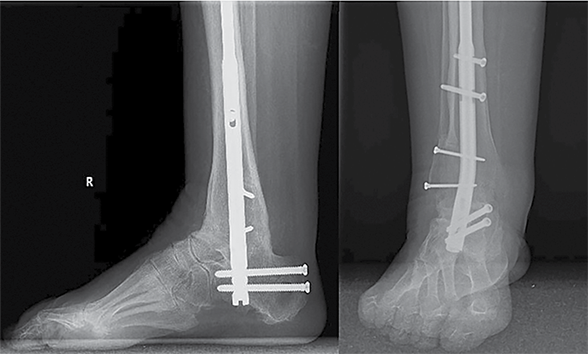

Antruoju atveju 38 m. pacientė kreipėsi į LSMU KK dėl deformuotų pėdų. Deformacijos prasidėjo vaikystėje. Dėl deformacijų sunku eiti, krypsta kojos, sunku pritaikyti tinkamą avalynę. Tais pačiais metais diagnozuota CMT liga. Objektyviai matyti abiejų pėdų varus deformacija, subtalarinių sąnarių nestabilumo požymiai. Vertinant objektyviai: pėdos plantarinė fleksija ‒ 25°, dorsifleksija ‒ 5°. Prieš 20 m. atlikta abiejų pėdų I tarsometatarsalinių (TMT) sąnarių artrodezės, susiformavusi kaulinė ankilozė. Rentgenogramoje matyti abiejų čiurnos sąnarių I stadijos artrozė, varus tipo pėdų deformacija, aukštas pėdos skliautas. Pacientei taikytas konservatyvus gydymas buvo neefektyvus. Skausmo nejaučiama. Pagal EFAS čiurnos ir pėdos funkcijos vertinimas siekė 18 balų, pagal AOFAS – 62 balus. Siekiant sustabdyti pėdos deformacijų progresavimą, atlikta kairiojo kulnakaulio ašį koreguojanti osteotomija ir subtalarinio sąnario artrodezė dviem sraigtais, Hoke metodika pailginta Achilo sausgyslė, atlikta lateralinių čiurnos sąnario raiščių plastika naudojant inkaruojantį sraigtą, I padikaulio uždaro kampo kylinė osteotomija bei osteosintezė L formos 5 skylių plokštele ir 4 rakinamais sraigtais. Po operacijos rekomenduota 2 savaites laikyti koją pakeltą, imobilizuoti įtvaru 10 savaičių, neminti kojos 8 savaites, o vėliau palaipsniui didinti atraminį krūvį. Po 4 savaičių, išėmus koją iš įtvaro, mankštinti ją per čiurnos sąnarį ‒ čiurną lenkti ir tiesti, vengti sukti pėdą į šonus. Po 6 savaičių paskirta atvykti ortopedo-traumatologo kontrolinės konsultacijos. Reabilitaciją numatyta pradėti po 10 savaičių. Po metų rentgenologinėse nuotraukose matyti gera konstrukcijų padėtis, sugijusios osteotomijų zonos ir susiformavusi kaulinė ankilozė. Pagal EFAS ‒ 23, pagal AOFAS – 82 balai. Vertinant objektyviai: pėdos plantarinė fleksija ‒ 35°, dorsifleksija ‒ 10°.

6 pav. Kairės čiurnos ir pėdos rentgenogramos praėjus metams po operacijos

Po metų pacientė atvyko dėl dešinės pėdos nestabilumo, sunkumo vaikščioti. Sudėtinga pritaikyti avalynę, konservatyvus gydymas neefektyvus. Rentgeno nuotraukose matyti dešinės pėdos varus tipo deformacija, aukštas pėdos skliautas. Čiurnos ir pėdos funkcija pagal AOFAS – 67 balai, pagal EFAS – 18 balų. Pacientei atlikta uždaro kampo kulnakaulio ašį koreguojanti osteotomija, lateralizuotas gumburas, atlikta subtalarinio sąnario artrodezė dviem sraigtais. Hoke metodika pailginta Achilo sausgyslė. Atlikta I padikaulio uždaro kampo kylinė osteotomija ir osteosintezė L formos 5 skylių plokštele ir 4 rakinamais sraigtais. Po operacijos koja imobilizuota gipso langete, skirti analgetikai ir vaistai nuo trombų susidarymo. Pritaikytas ortopedinis įtvaras. Rekomendacijos išliko tokios pat, kaip ir po kairės kojos operacijos. Kontrolinės apžiūros duomenų dar negalima vertinti, nes operacija atlikta neseniai.

7 pav. Dešinės čiurnos ir pėdos rentgenogramos po operacijos